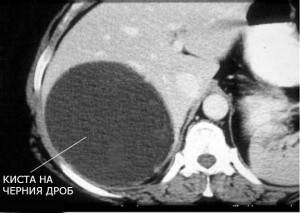

Кистите могат да бъдат разположени в различни сегменти и дялове на черния дроб, да бъдат на повърхността и в дълбочина. Диаметърът на кистите може да достигне до 25 см, рядко се случва, но се срещат кисти с дори по-големи размери. Допустимо е и киста да се появява на фона на други заболявания като: цироза на черния дроб, камъни в жлъчката, поликистоза на бъбреците, поликистозни яйчникови кисти, кисти на жлъчните пътища и други.

кисти на черния дроб се делят на истински и фалшиви кисти. Истинските кисти могат да се появят, ако все още в утробата не се свързват отделни жлъчните канали на системата на жлъчните пътища. Установява се чрез ултразвук или компютърна томография на черния дроб на случаен принцип.